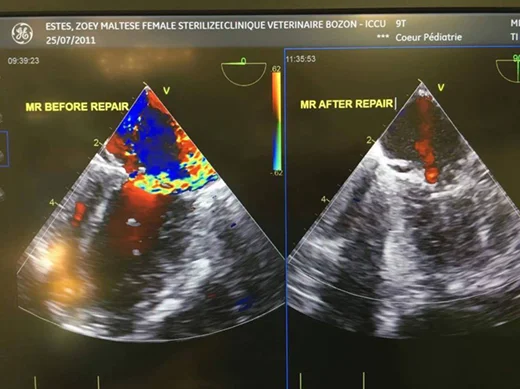

Prior to surgery, Zoey’s heart was extremely large and her left atrium vein was dilated and stretched.

The surgery also revealed she was almost going to have a chord rupture. Once this is healed, her heart will continue to shrink and her murmur should reduce as well.

The goal of this surgery is to restore them to the B1 stage and repair the valve as much as possible to reduce the regurgitation.